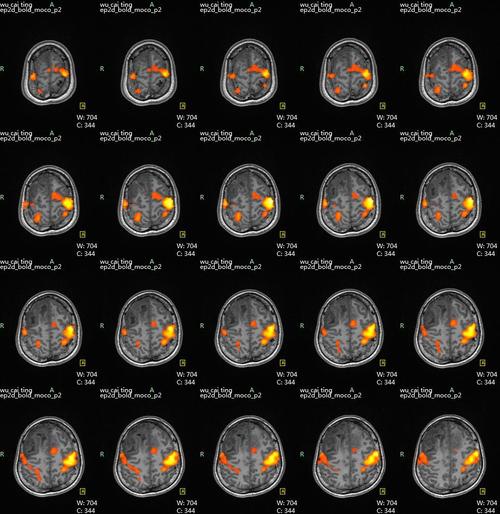

研究脑功能映射(Function Brain Mapping)有许多成功的模式(Modality),例如正电子发射断层扫描(Positron Emission Tomography,PET),在向脑内注射15O水后,通过测量局部脑血流(rCBF)的方法来检测大脑的活动。脑电图(EEG)和脑磁图(MEG)也可检测大脑对诱发刺激响应的电或磁信号,但很难对活动区作准确的空间定位。实验使用功能核磁共振对被试的脑区功能映射,功能磁共振成像(Functional MRI)是一种非常有效的研究脑功能的非介入技术,已经成为最广泛使用的脑功能研究手段。它虽然是一种非介入的技术,但却能对特定的大脑活动的皮层区域进行准确、可靠的定位,空间分辨率达到1mm,并且能以各种方式对物体反复进行扫描。FMRI能实时跟踪信号的改变,在仅几秒钟内发生的思维活动,或认知实验中信号的变化。

功能核磁共振

被试在功能核磁共振中给予色情视频的刺激,研究被试大脑激活的差异。通过磁共振控制室的玻璃窗口将录像投影到玻璃上,而被试可以通过线圈顶部的反射镜观看到*放播**投影的图像。